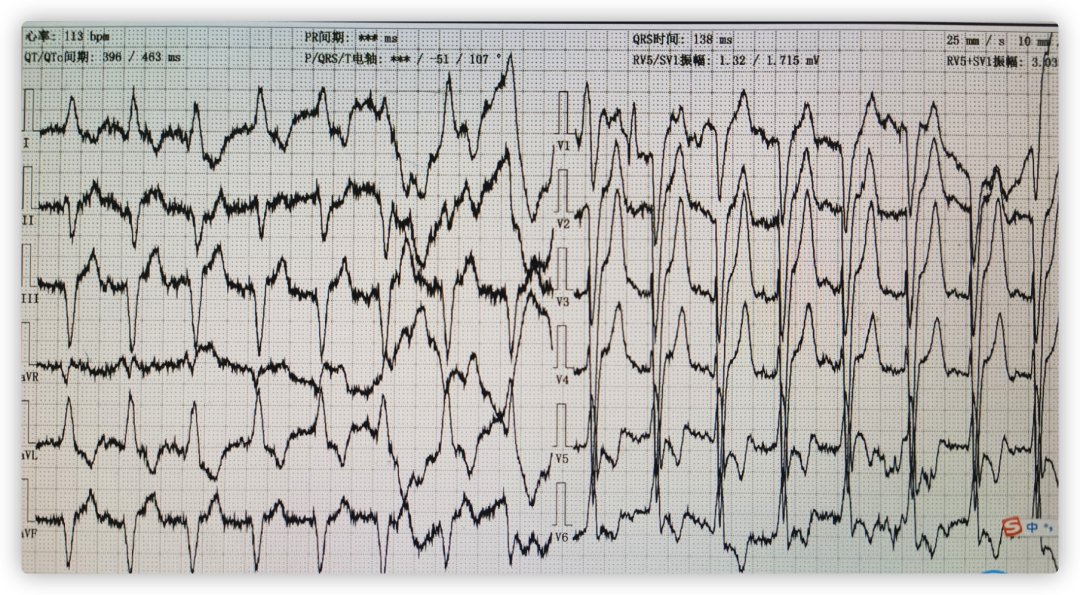

ECG术前

ECG术后即刻

ECG出院时